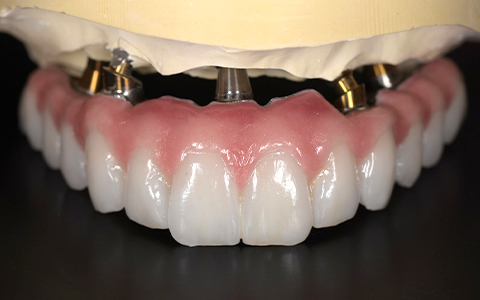

オールオン4+α(All-on-4+α)とは、上下に最少4本ずつのインプラントを埋入し、総入れ歯の形をした上部構造を固定して短時間で見た目と噛み合わせ機能を回復させる治療法です。

とびきり美しい上部構造

ただ治すのではなく、美しく治す。しかも、とびっきり美しく治すことにこだわっています。そのため、数々の賞を受賞する腕の良い歯科技工士と連携して歯をデザインしています。